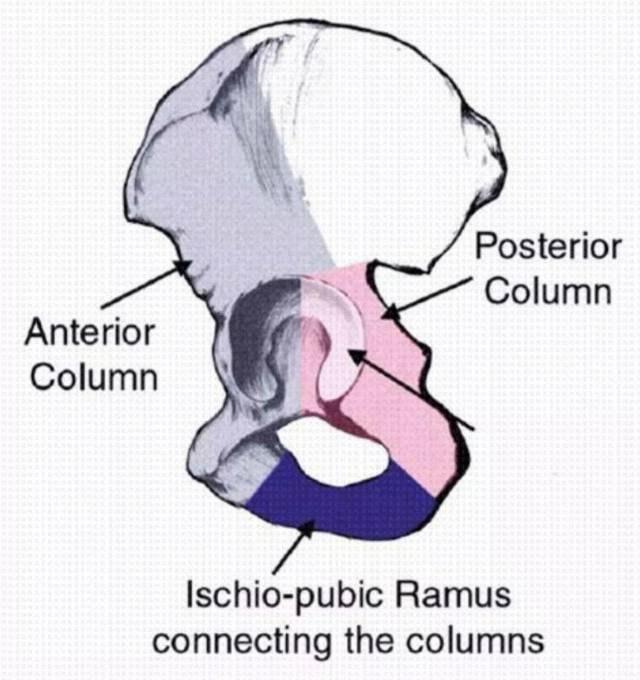

髋臼骨折分型

髋臼骨折分型

640x680 - 52KB - JPEG